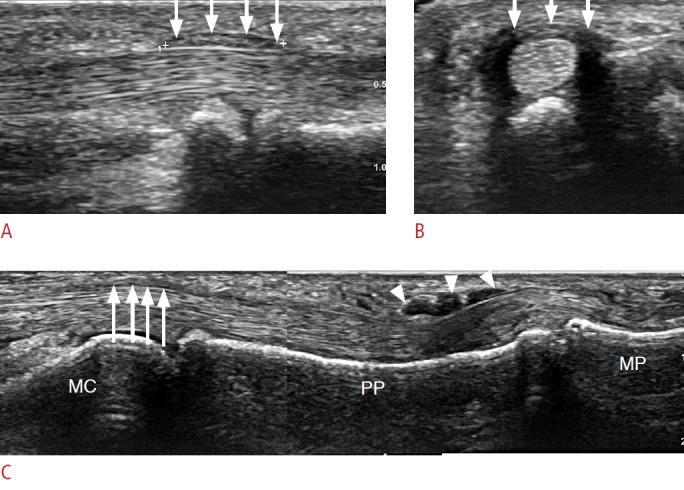

The recent development of advanced high-resolution transducers has enabled the fast, easy, and dynamic ultrasonographic evaluation of small, superficial structures such as the finger. In order to best exploit these advances, it is important to understand the normal anatomy and the basic pathologies of the finger, as exemplified by the following conditions involving the dorsal, volar, and lateral sections of the finger: sagittal band injuries, mallet finger, and Boutonnière deformity (dorsal aspect); flexor tendon tears, trigger finger, and volar plate injuries (volar aspect); gamekeeper's thumb (Stener lesions) and other collateral ligament tears (lateral aspect); and other lesions. This review provides a basis for understanding the ultrasonography of the finger and will therefore be useful for radiologists.

先进的高分辨率换能器的最新发展使得对手指等小而浅表结构进行快速、简便和动态的超声评估成为可能。为了充分利用这些进展,了解手指的正常解剖结构和基本病变非常重要,以下列举了累及手指背侧、掌侧和侧方的一些情况,包括:矢状带损伤、锤状指和纽扣畸形(背侧);屈肌腱撕裂、扳机指和掌板损伤(掌侧);守猎者拇指(斯滕纳损伤)和其他侧副韧带撕裂(外侧);以及其他病变。这篇综述为理解手指的超声检查提供了基础,因此对放射科医生非常有用。